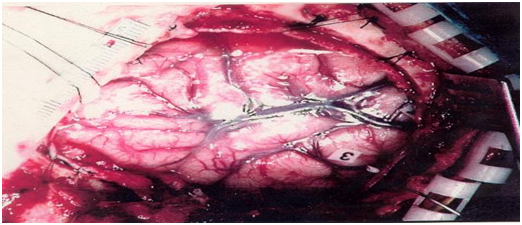

Figure 3 during resection surgery in the epilepsy patient, the BRODERICK PROBE® nanobiosensor, smaller than one human hair, is placed, intra operatively, directly on the exposed brain of the epilepsy patient in the anterior temporal lobe of patients’ brain. Readily seen is what is called, the “Great Vein”.

In the first part, this novel nanotechnology that senses the brain is comprised of the potentiostat detector, the nanobiosensor input and electrochemical detection as seen online as computer image, described in Figure 1 and Figure 2. In the second part, the novel nanotechnology that senses the brain is comprised of a dual photo-laser diode protein based nanobiosensor input and fiber optics input for electrochemical spectroscopic output detection. Figure 4 shows a schematic of a generic photodiode. Figure 2 shows the live resected hippocampus surgically removed after study. The live temporal lobe in the epilepsy brain is shown, exposed, intraoperatively in Figure 3. A schematic diagram of the generic BRODERICK PROBE® is shown in Figure 1.

Figure 3 The exposed brain is which the BRODERICK PROBE® nanobiosensor is placed.